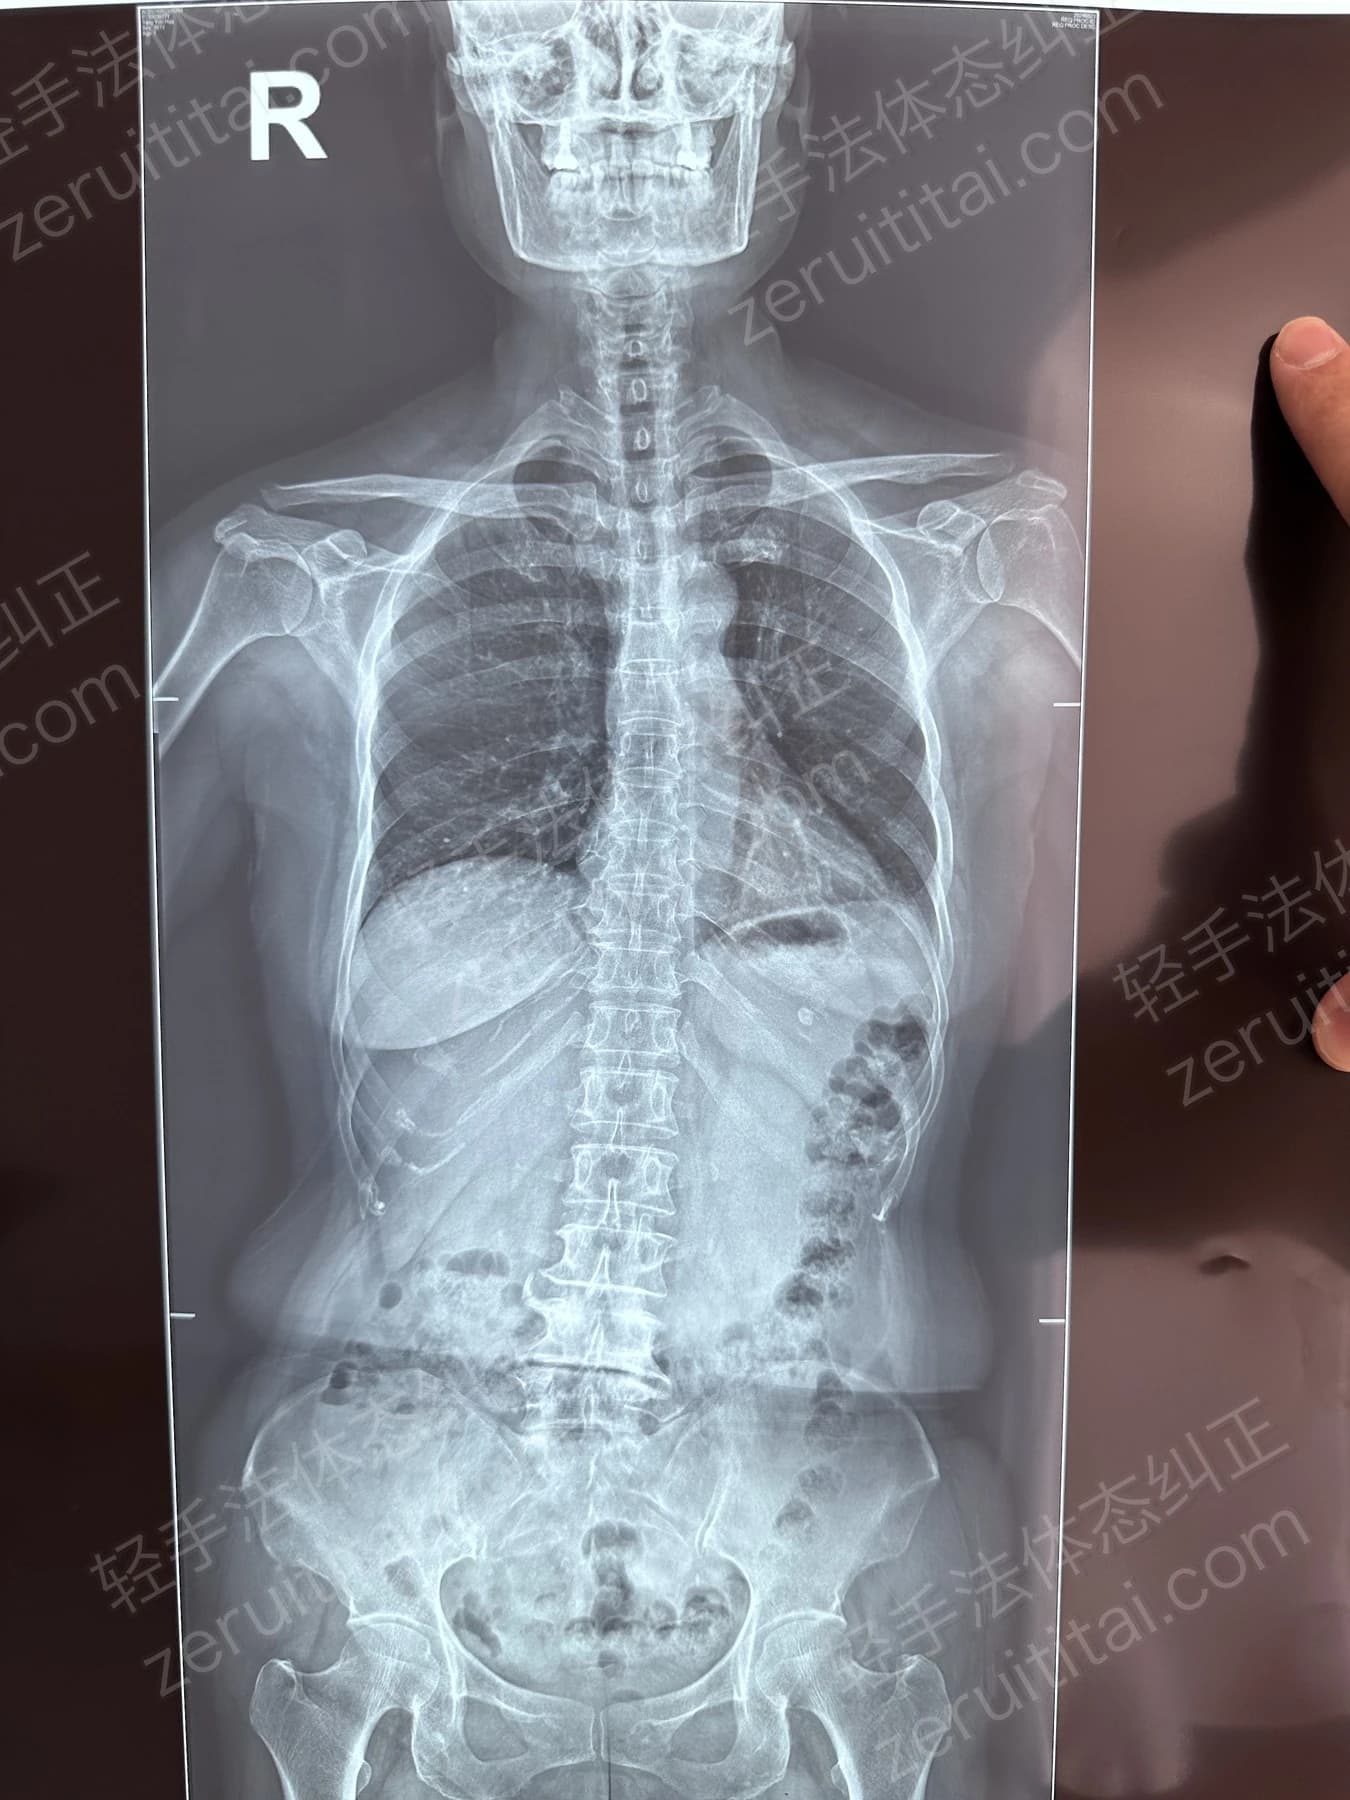

2023.05.30

第 4 次记录